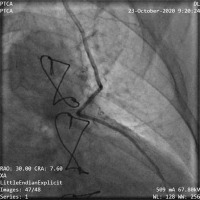

In such cases, for the last 6 years, a method with angiographic balloon occlusion of the LIMA has been used. All patients had previously undergone LIMA grafting of the left anterior descending coronary artery, and, in all cases, preoperative angiography had confirmed the patency of the graft. After signing informed consent forms, the patients were taken to the cardiac catheterization laboratory immediately before reoperation. A common left-femoral approach was used, and systemic heparin (70 IU/kg) was administered. A 6F sheath was placed and an IMA guide catheter was inserted to cannulate the IMA and to obtain posteroanterior and left anterior oblique angiographic views of the IMA graft. The IMA size, estimated visually, varied from 2.0 to 3.5 mm in our patients (Figure 1). A Hi-Torque Balance 0.014-inch coronary guidewire was then positioned into the IMA, followed by an over-the-wire balloon that was 15 mm long with a nominal diameter of 2.0 to 3.5 mm. The balloon was briefly inflated at the nominal pressure (6 atm), and angiography was performed to ensure occlusion of the LIMA graft (Figure 2). The balloon was then left, deflated, in a relatively straight segment of the proximal IMA.